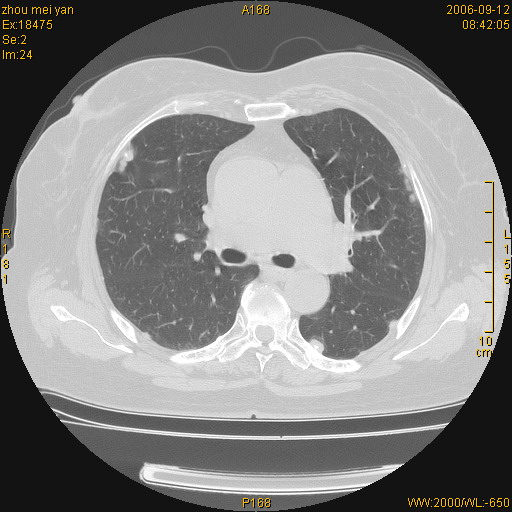

患者、女、55岁。因心率失常住院检查ct发现胸部多发结节。腹部b超肝、胆、胰、脾、肾、子宫附件未见异常。无结核病史,无粉尘接触史。请大家来会诊。谢谢!

双侧胸膜多发结节,形态不规则,边缘较清楚,每一个结节中心似乎都有钙化点的特征,与胸膜广基相切。临床无结核病史,无粉尘接触史。

影像表现十分有特点:双侧肋胸膜及膈胸膜广泛散在分布大小在2至6mm左右,较大病灶中心可见钙化。

病变位于胸膜,多发结节,边界清楚,内见小结节状钙化。其它未见异常。

考虑恶性胸膜间皮瘤可能性大,病灶位于胸膜,以宽基地与胸膜相连,呈结节样改变,部分病灶内可见点状钙化影。请各位老师多多指导!

双侧肋胸膜及膈胸膜广泛散在分布大小不等结节影,较大病灶中心可见钙化。

如果有类风湿性心脏病,就要高度怀疑是:类风湿性胸膜结节。疑问:病人血沉不快,是不是类风湿稳定期?另外病人肺内无明显纤维化改变,肺野内清晰,不符合类风湿肺内改变。